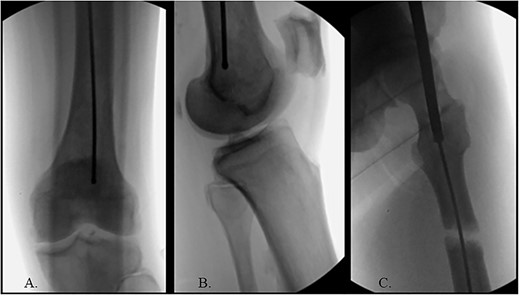

The hip was extended, and a ball-tipped guidewire was successfully passed across the fracture site to a center–center positionwithin the canal at the level of the knee (Fig. 4C and D). Sequential 0.5-mm reaming from 9 to 13 mm prepared for an 11 × 400 mm, 125° Gamma3® intertrochanteric rod (Stryker© Kalamazoo, MI), with a 95-mm cephalomedullary screw and ×2 distal lateral to medial interlocking 5.0-mm screws (Fig. 5A–D). Through the course of the procedure, 400 cc of blood loss necessitated two units of packed red blood cells.

(A) AP radiograph of left hip with implant; (B) lateral radiograph of left hip with implant; (C) reduced fracture site with implant; (D) distal femur with implant.